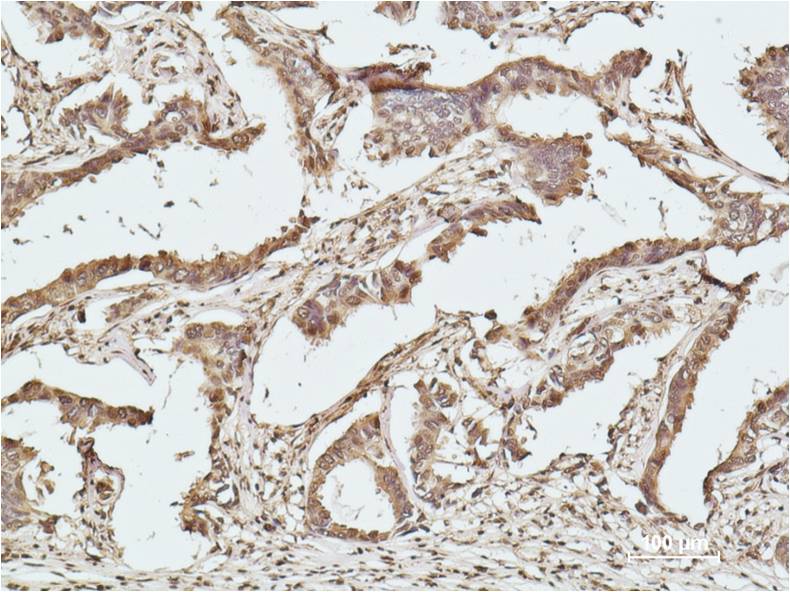

Immunohistochemical analysis of paraffin-embedded human breast caricnoma using Histone H2B (EM1163)Mouse mAb diluted at 1:500.